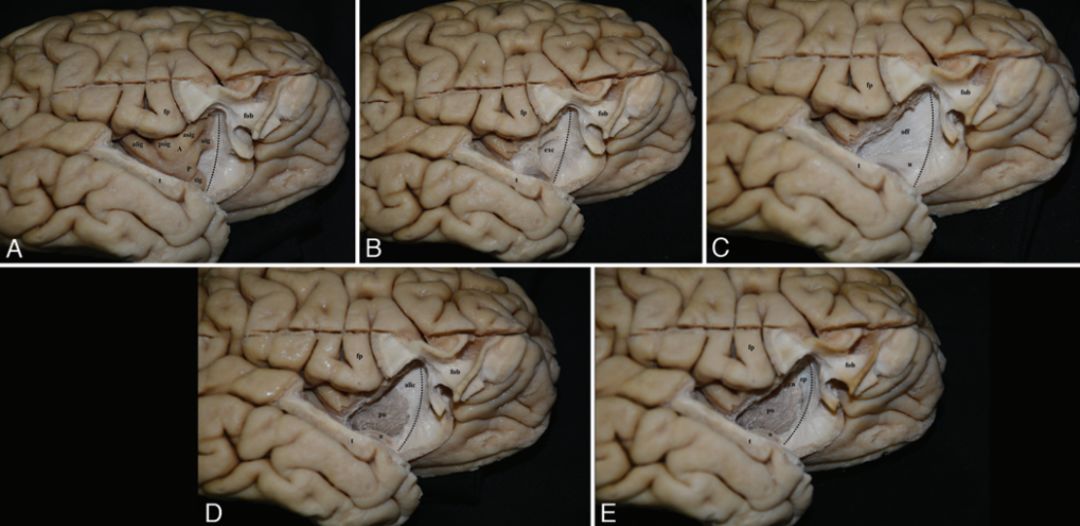

前峡部是指前环岛沟与侧脑室额角之间的白质带。此区域的纤维束解剖复杂,切除部分眶额回和颞盖,暴露岛顶和岛叶前表面(图1A)。沿岛横回和岛副回剥离岛顶灰质显示最外囊,最外囊构成前峡部白质的第一层。分离最外囊,前峡部第二层由枕额束前部、钩束及外囊的混合纤维组成(图1B)。在第二层水平,枕额束占前峡部的2/3,而钩束占1/3(图1C)。壳核和内囊前肢上方的灰质,这形成了前峡部的第三层(图1D)。分离内囊前肢显示额角室管膜和尾状核头(图1E)。前峡部内侧界由额角上缘、壳核和尾状核头下缘组成。前峡部的平均长度和宽度分别为29.2mm和7.6mm。

图1.逐层解剖右侧半球前峡部内外侧面,黑色虚线表示在前环岛沟水平。A:前环岛沟,切除部分眶额回和岛盖,显露岛顶和岛叶前表面;B:剥离岛顶、岛横回和岛副回灰质,显示最外囊,为前峡部白质第一层;C:分离最外囊,显露枕额束和钩束,组成前峡部第二层;D:在前峡部水平继续分离,显露内囊前肢纤维,即前峡部的第三层;E:额角室管膜是前峡部解剖分离终止的标志,尾状核头与额角相邻。